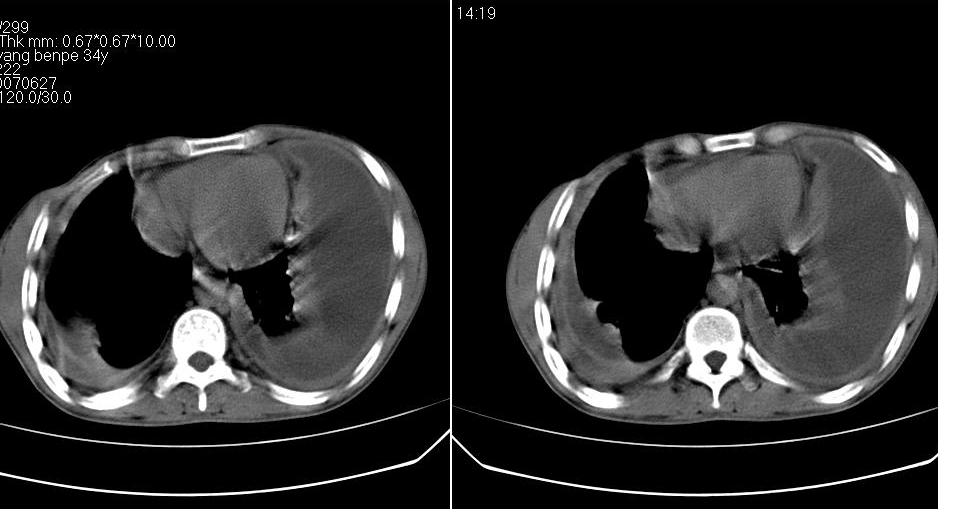

以下是引用苯小孩在2007-6-27 15:09:00的发言:[br]考虑:1、右肺继发性肺结核.2、双侧包裹性积液<胸腔及叶间>3、双侧局部胸膜增厚.[br]建议胸水化验检查.

以下是引用yanghaochen88在2007-6-27 15:08:00的发言:[br]双肺上野散在粟粒状影、包裹性积液、胸膜增厚粘连、叶间积液---tb,至于分型还得结合病史体征细究妥当些。

以下是引用zjzjr在2007-6-27 16:49:00的发言:[br]肺结核、结核性胸膜炎。